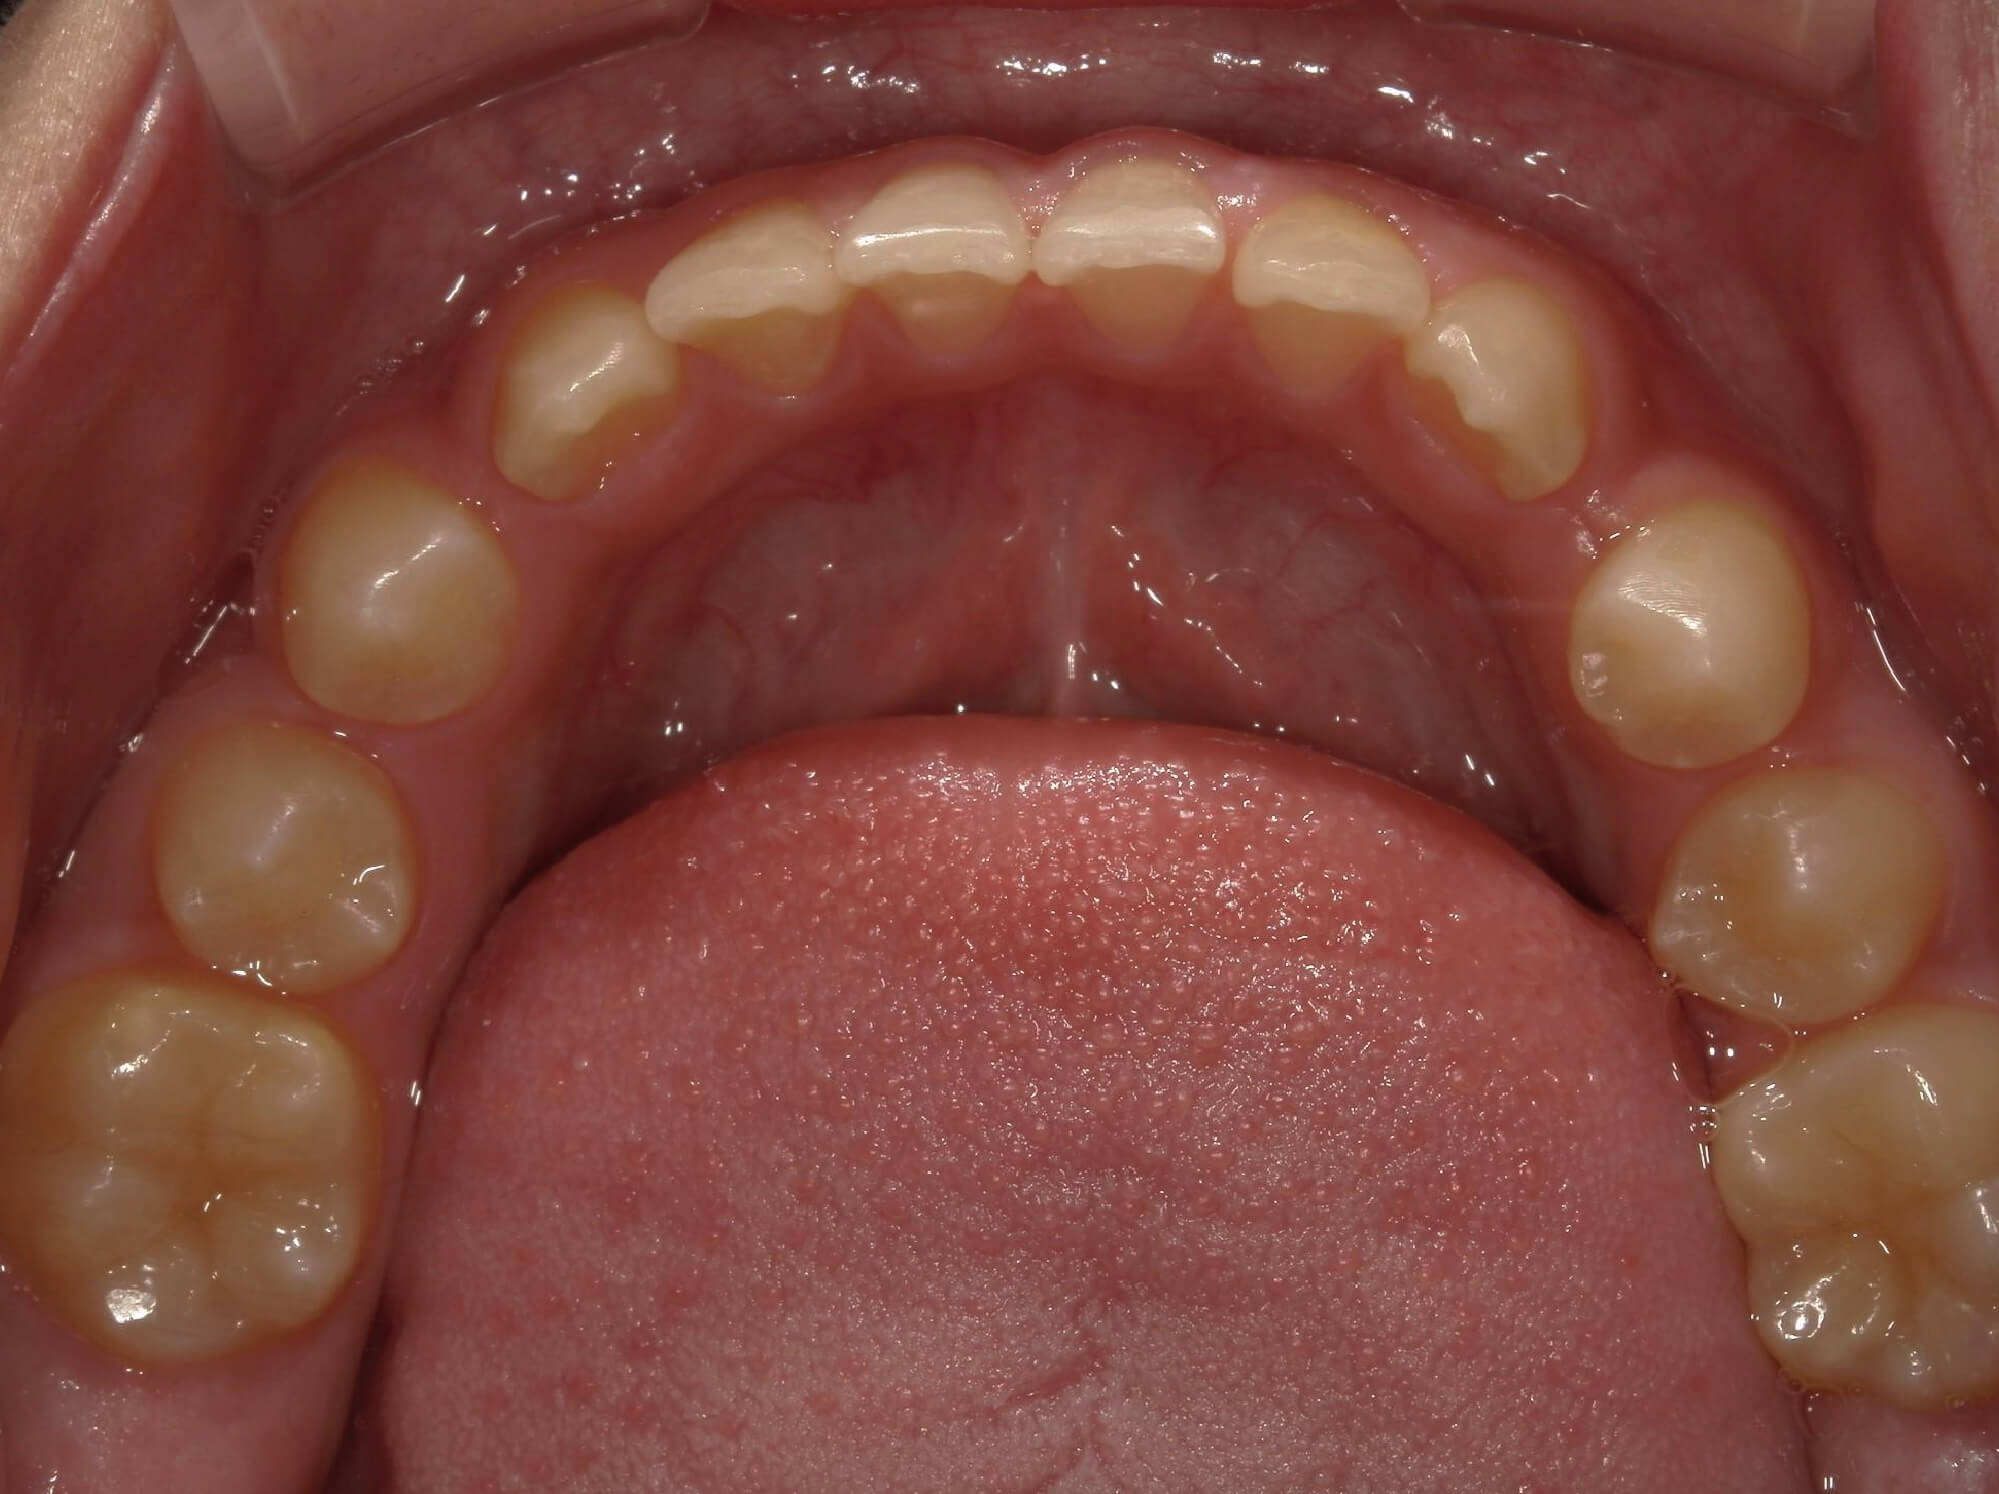

| 年齢・性別 | 7歳1ヶ月の男児 |

|---|---|

| 主訴 | 歯の生えるスペース不足が懸念され、歯列の乱れ(叢生)を整えるために来院された患者様です。 |

| 治療期間・回数 | 1年3ヶ月・11回 |

| 費用 | 420,000円(税別) |